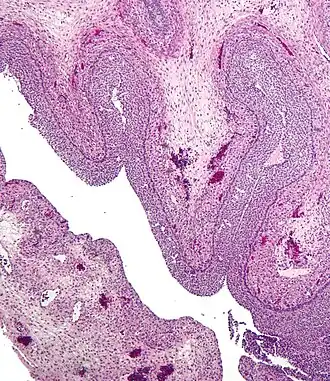

Luteinized follicular cyst. H&E stain.